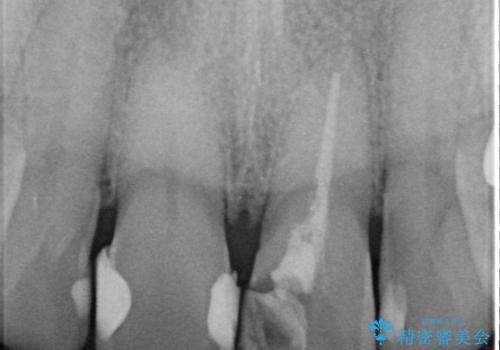

- 歯髄が死んで変色していた歯に対して、根管治療とオールセラミッククラウンでの修復を行いました。まず、根管治療で内部の感染を除去し、歯の強度を高めるためにファイバーコアを装着しました。その後、審美性と耐久性を考慮し、オールセラミッククラウンで覆うことで、自然な歯の色合いに近い美しい仕上がりを実現しました。

歯髄が死んだ歯は通常の健康な歯に比べて透過性が低く、特有の暗い色調を帯びる傾向にあります。変色は時間とともに進行し、薄い茶色や灰色、黄色がかった色合いになることが多いです。このような変色は、審美的な面で気になる場合が多く、オールセラミッククラウンなどでの修復が行われることも一般的です。